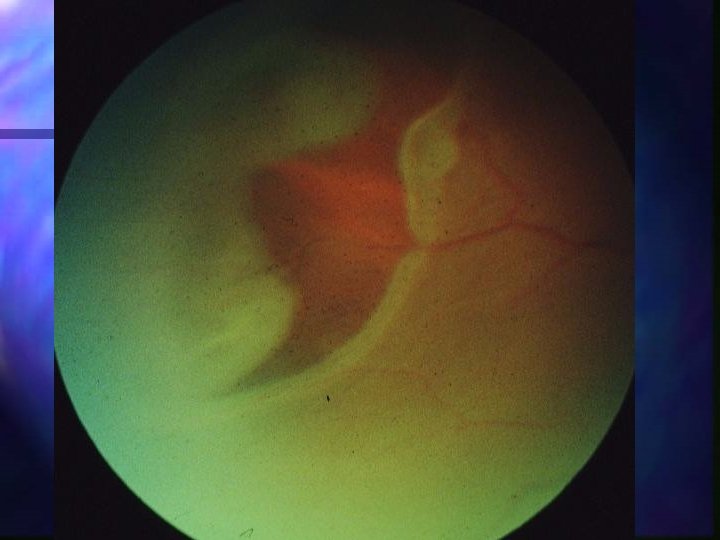

Choroidal rupture n Bruch’s membrane often tears n At point of contact or at posterior pole n Clinically looks like subretinal hx May dissect into vitreous n Becomes white crescent-shaped area with RPE atrophy n n Should follow pt for risk of CNV